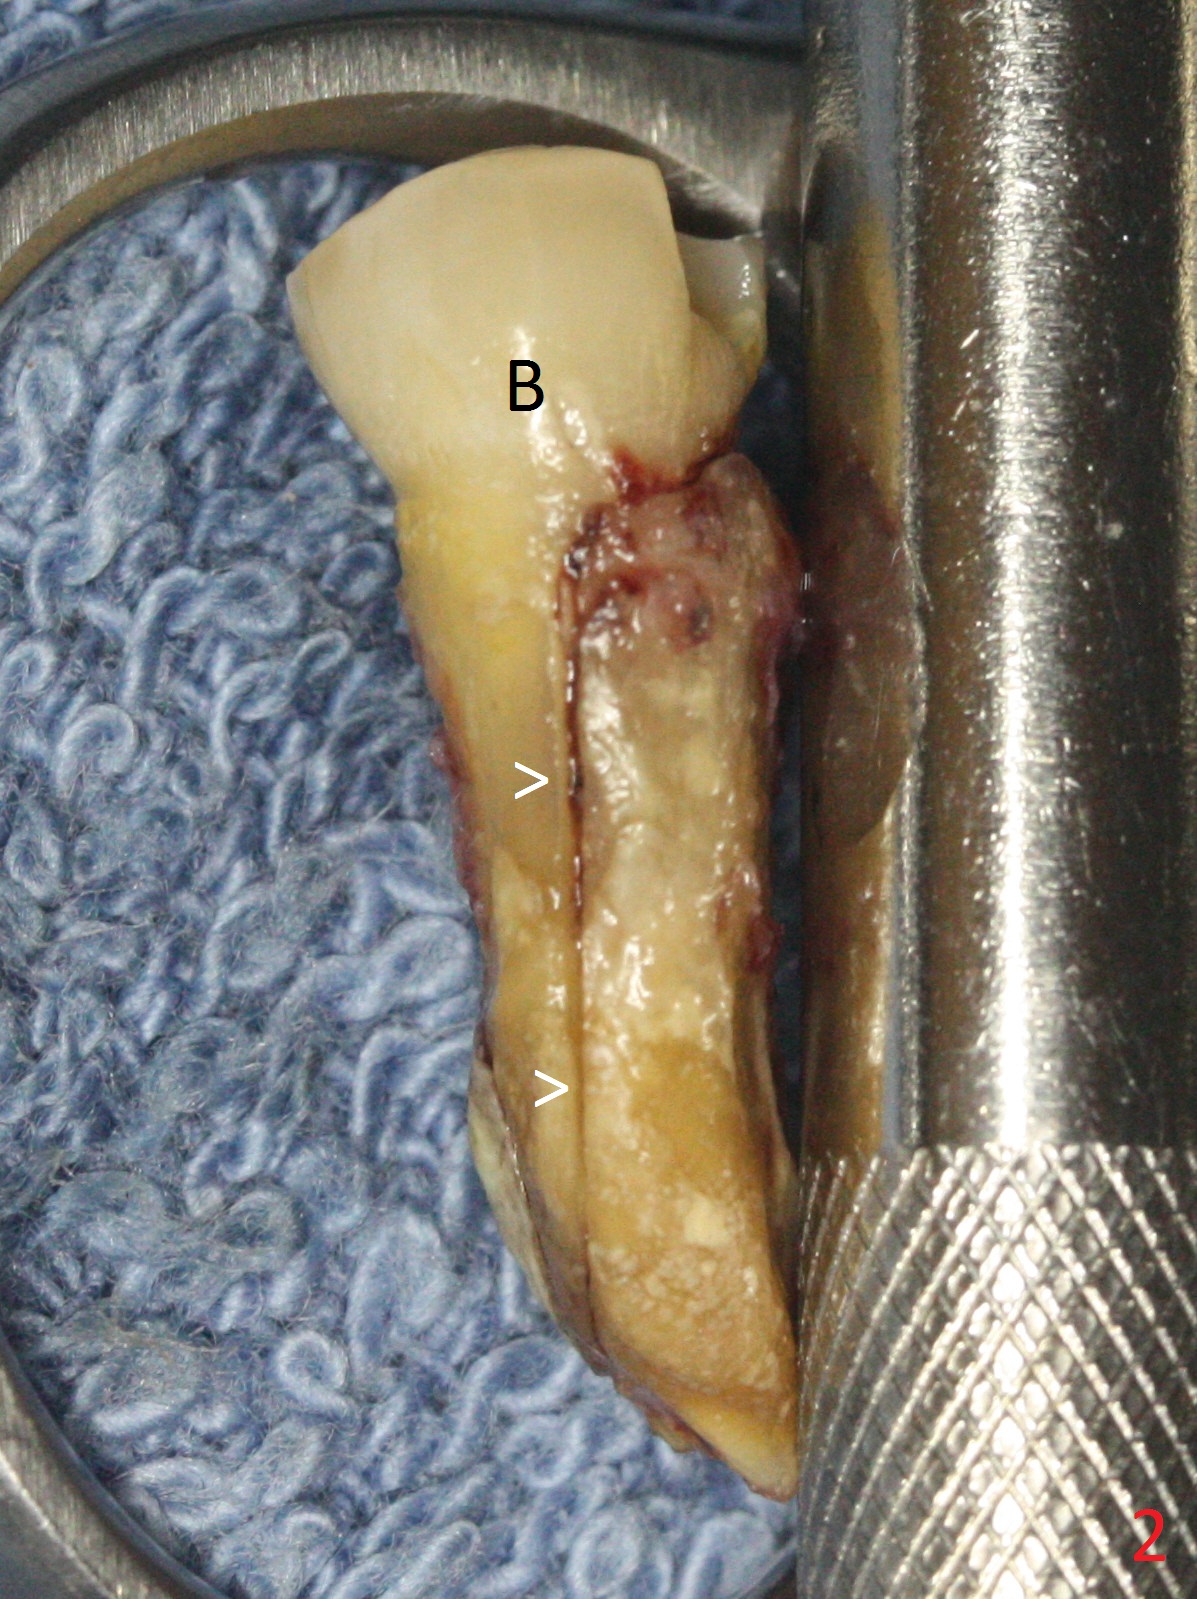

Extraction of the lower left 2nd premolar with vertical fracture (Fig.1,2 >) is easy because of peri-radicular radiolucency. The apical end of the osteotomy is not shown with a 2 mm pilot drill (Fig.3) or a 3.8x18 mm implant (Fig.4) in place. It appears that the implant is not placed deep enough. Following 3-4 more turns of the implant and placement of a 5.5x4(3) mm abutment (Fig.5 A), allograft is placed (*). A postop panoramic X-ray is taken (Fig.6); the osteotomy could have been deepened to reduce the possibility of periimplantitis. Retrospectively, the panoramic X-ray should be taken after use of the pilot drill. The bone around the implant appears to have regenerated 4 months postop (Fig.7,8). Bone density appears to continue increasing 9 months postop (i.e., 4.5 months post cementation, Fig.9). Bone loss is minimal 2 years post cementation (Fig.10).